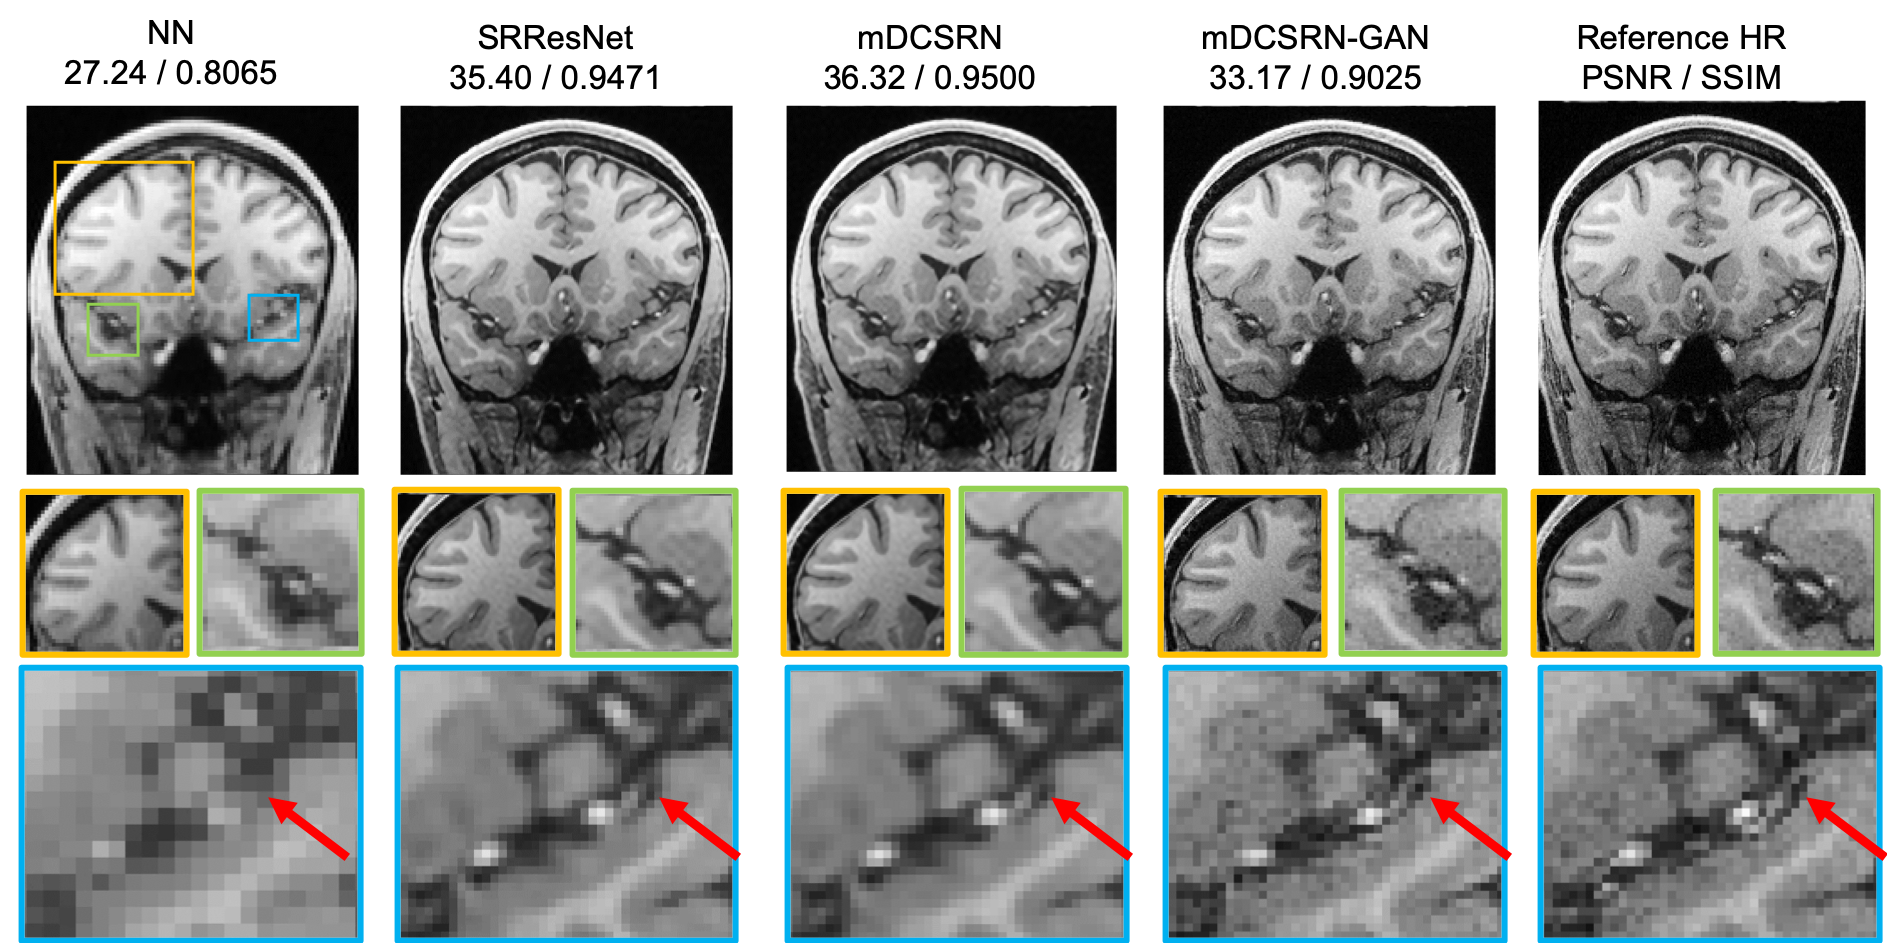

Figure 6: Example results from the test set of Nearest Neighbor, SRResNet, mDCSRN b8u4𝑏8𝑢4b8u4, mDCSRN-GAN b8u4𝑏8𝑢4b8u4 in the 2×2222\times 2 resolution degraded plane. PSNR and SSIM of this subject are shown on the top. Despite performing worse in PSNR and SSIM, GAN SR images appear to have recovered more spatial details.

Baseline. As baseline models, FSRCNN (Dong et al., 2016b), SRResNet (Ledig et al., 2017), and SRDenseNet (Tong et al., 2017) were implemented and extended to 3D. As there is no image-size changing in our SISR, the up-sampling CNNs (transposed-convolutional layers or sub-pixel layers) in those original designs were replaced with the same scale convolutional layers. For SRDenseNet, we adjusted the hyperparameters as similiar as possible to mDCSRN b8u4𝑏8𝑢4b8u4 (i.e. reduced DenseUnit number from 8 to 4, changed activation function to ELU, and set growth-rate k=12). All models were trained for 300 epochs. With respect to quantitative similarity metrics, as shown in Table 2, the lightest mDCSRN b4u4𝑏4𝑢4b4u4 ran fastest among all CNN approaches with competitive results. The deepest mDCSRN b8u4𝑏8𝑢4b8u4 as shown in Fig. 6 outperformed all previous SISR approaches by a considerable margin. It did run slower than SRDenseNet but was still 4x faster than the SRResNet. Both SRDenseNet and mDCSRN b6u4𝑏6𝑢4b6u4 are similar in model size and running speed, but the later significantly outperformed the former, proving the advantage of our efficient architecture design.

Perceptual Quality. An example output is shown in Fig. 6. mDCSRN b8u4𝑏8𝑢4b8u4 provides slightly better SR reconstruction accuracy than SRResNet, but it is mDCSRN-GAN b8u4𝑏8𝑢4b8u4 that more closely shapes the small vessel pointed by the red arrows. Though mDCSRN-GAN’s PSNR is lower than its non-GAN sibling, it provides more structural details that are more plausible by the human eye. As shown in Table 2, the quantitative perceptual quality numbers suggest that while non-GAN SR shows slightly closer to HR only in the MA’s metric, the GAN SR model shows much better performance in all other three measurements. GAN even obtained a higher score in NIQE and PI than HR, since SR images were generated from less noisy LR input, making the SR more plausible for noise-sensitive perceptual metrics. Wang et al. (2018) has shown similar results in their SR and HR perceptual comparison.